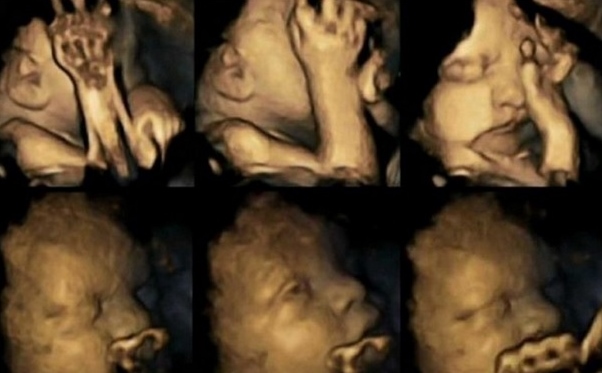

Estudo britânico mostra efeitos nocivos do tabagismo na gravidez. Ecografias 4D revelaram reações dos bebês no útero quando as mães fumavam; resultado mostrou que eles tendem a fazer mais ‘caretas’ e movimentos da boca e das mãos

Ao observar 80 ecografias em 4D de 20 bebês, os pesquisadores descobriram que os fetos cujas mães eram fumantes apresentaram uma taxa significativamente maior de movimentos da boca em comparação com os níveis normais. A razão para essas reações pode estar no sistema nervoso central, que controla os movimentos em geral e, em particular, os faciais.

Assim como em outros estudos, a pesquisa também mostrou que estresse e depressão materna também impactam sobre os movimentos fetais. Mas houve aumento dos movimentos da boca e das mãos em bebês cujas mães fumaram.